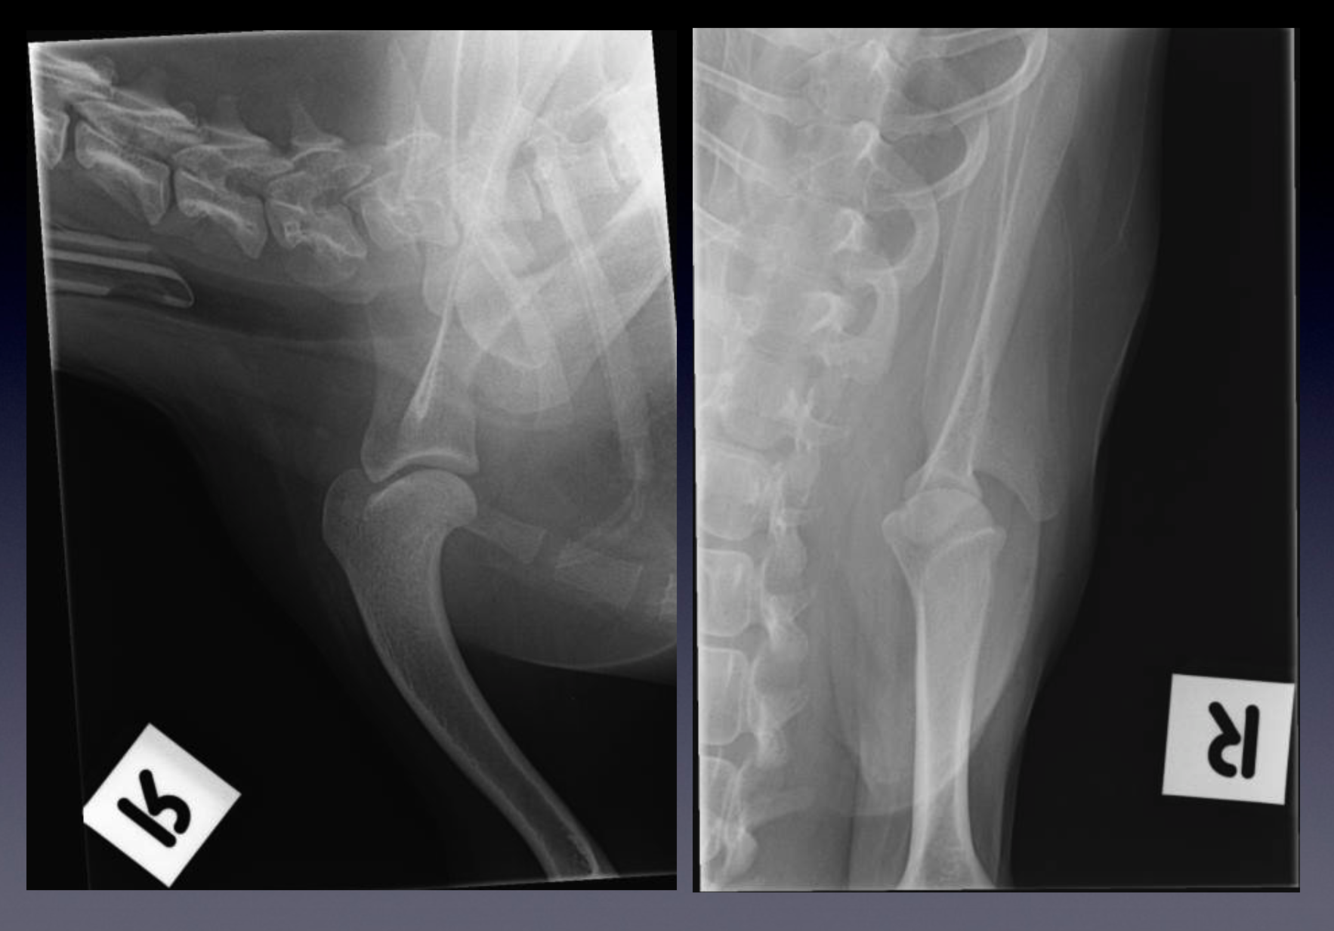

Patient number 245702 - Normal Canine Pelvis

WHAT VIEWS ARE THESE?

Assess Positioning:

•

On the lateral view, use the transverse processes of the vertebrae, and alignment of the two hemipelvises

On the VD view, use the dorsal spinous processes, size and shape in the iliac wings, and symmetry of the

obturator foramina. The femurs should be parallel to each other and parallel to the table (how would you

judge this?). The patellae should be superimposed over the femoral trochlea, within the sagittal plane of the

femur. The fabellae should be roughly located over the femoral cortices.

The lateral projection:

is useful for evaluation of the position of femoral heads compared to acetabulae

is useful for evaluation of the lumbosacral area, especially when looking for the presence of transitional

vertebrae

The VD hip extended projection:

is the official view (by the Australian Veterinary Association, also the OFA in North America, BSAVA in Great

Britain, and FCI in Europe) for screening for hip dysplasia, so correct positioning is very important

is useful for evaluating the position of the femoral heads relative to the acetabulae

is useful for assessment of pelvic fractures

is useful for assessment of other boney pathology of the pelvis

Lateral and ventrodorsal (VD) hip-extended projection.